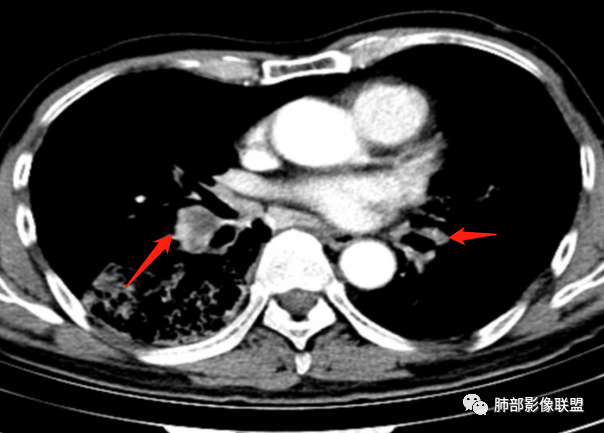

右肺下叶大团块影,斜裂膨隆,内支气管破坏,纵隔窗实质性成份少有强化(假大空),肿瘤CA125、199高,考虑粘液腺Ca右肺门淋巴结及纵隔淋巴结大,右肺下动干起始处充盈缺损(示栓塞或Ca栓;余肺叶弥散网格状改变,间质增厚及纤维化表现!

整个背景是一个肺气肿并间质纤维化,肺气肿以上肺为主(有些地方分不清到底是小叶中心或间隔下肺气肿伴间隔增厚还是蜂窝),左肺下叶正常结构消失,以弥漫网格为主,应该没有多少正常肺功能组织。右肺下叶肺动脉栓塞,再往下几层应该是肿大淋巴结并坏死。右肺下叶的病变考虑粘液性腺癌, 需与感染鉴别(有没有可能是肺梗死呢?)

淋巴结大,环形强化;淋巴结压迫支气管所致引流不畅?还是肺内病灶引起淋巴结肿大?

我是觉得支气管近端受压,远端不畅。就怕二元论,淋巴结独立,肺部独立。我倾向于二元,淋巴结独立,炎症继发。其实有前片就好办,炎症肯定变化大,癌变化不大。

右侧肺门淋巴结肿大,中央低密度;纵隔见轻度增大淋巴结。

3.综合分析:临床方面:慢性病程、急性发作,呼吸道症状伴发热,炎性指标升高,提示存在感染可能;CA199升高,但相对特异性不高。影像双肺气肿,右肺下叶蜂窝状改变明显,夹杂实变密度区,支气管相关但未见阻塞,较常见于感染性病变,如G-杆菌感染等。蜂窝影什么时候出现我们不得而知,实变区周边特征掩盖不清。

前后三月余病灶变化不明显,右肺门异常肿大淋巴结让人警惕恶性病变可能性。

显著肺门淋巴结肿大较少出现在粘液腺癌患者,何况如此大范围病灶未见播散结节。